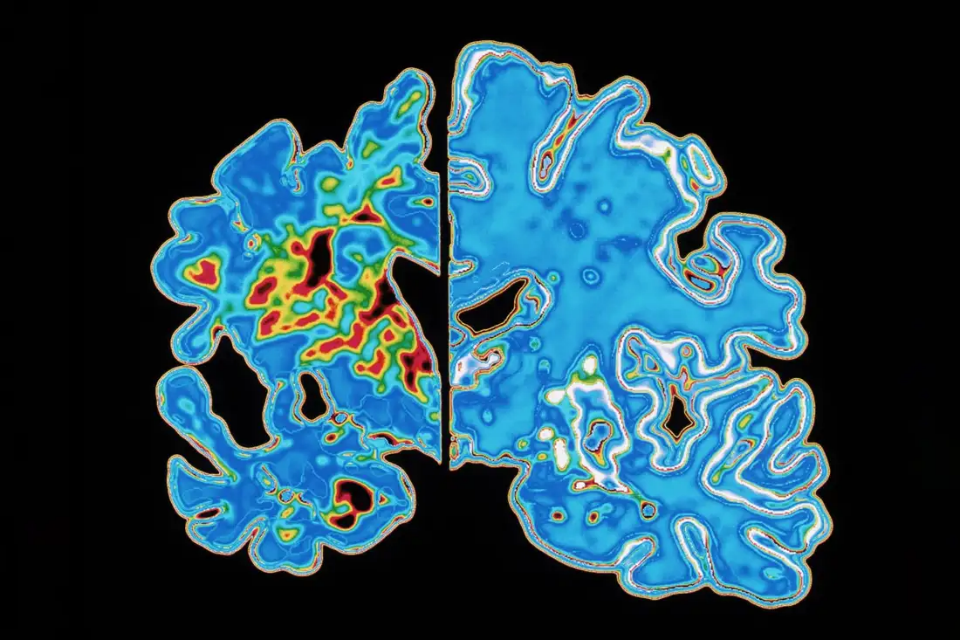

相比正常大脑(右),阿尔茨海默病患者的大脑(左)因神经细胞退化死亡而明显萎缩